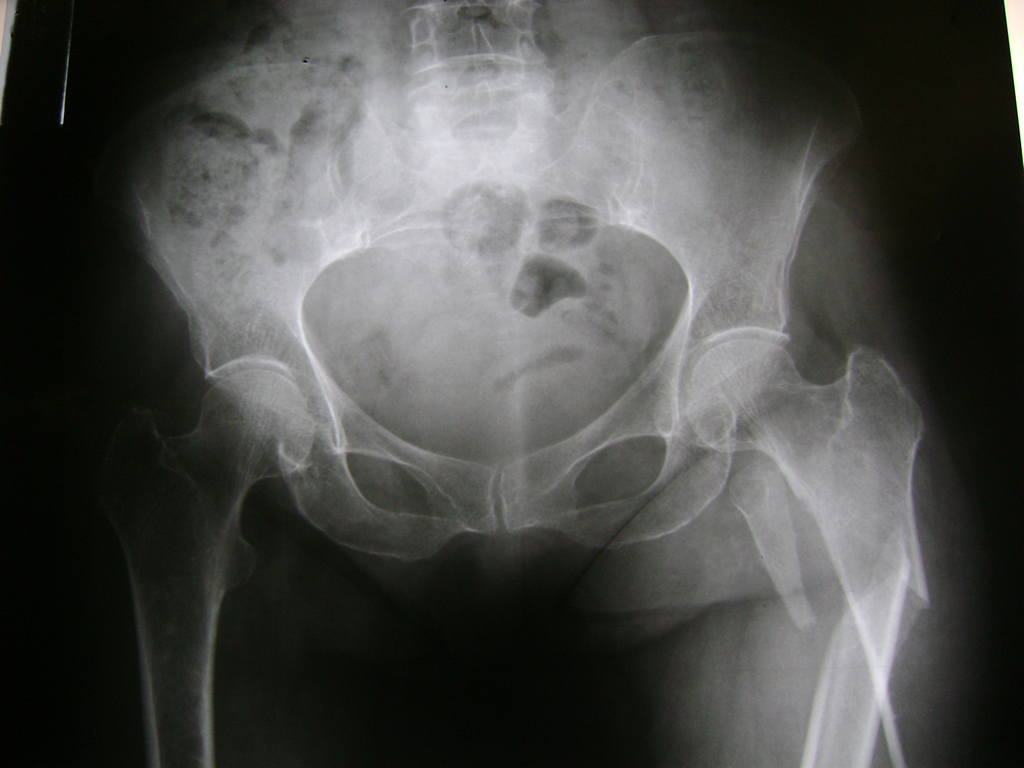

La cirugía de fractura de cadera se realiza para reparar una ruptura en la parte superior del hueso del muslo. Este hueso se denomina fémur.

Es parte de la articulación coxofemoral. Si una fractura de cadera no recibe tratamiento, es posible que deba permanecer en una silla o en la cama.

A menudo se recomienda la cirugía para reparar la fractura debido a dichos riesgos.